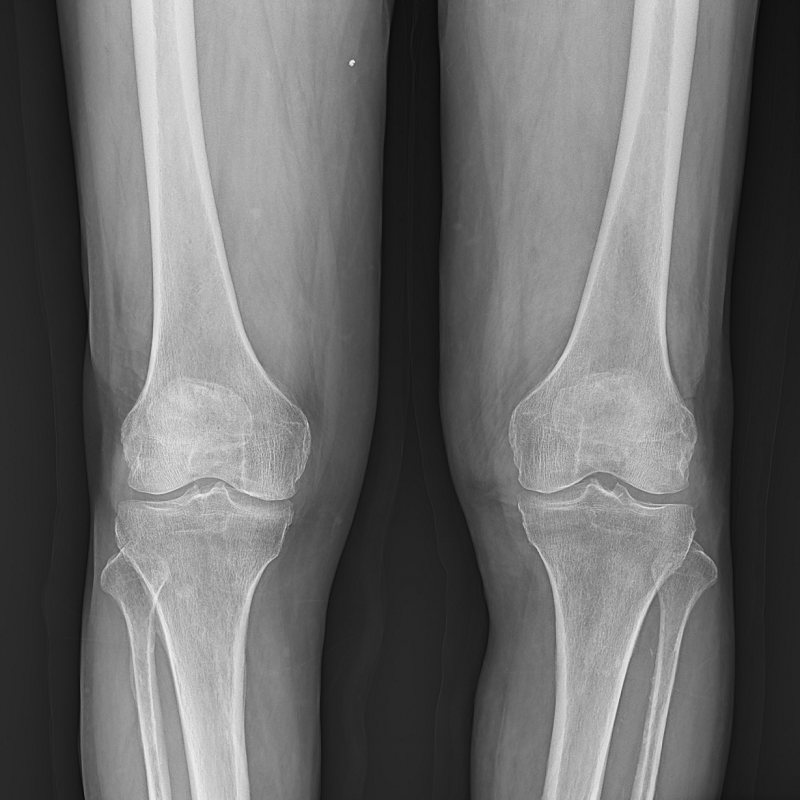

●呈現(xiàn)全下肢或全脊柱圖像

●在脊柱及下肢畸形矯正手術(shù)治療中,為術(shù)前方案制定和術(shù)后復(fù)查提供精準(zhǔn)測(cè)量

●有效解決傳統(tǒng)X光片不能一次成像問題,為患者提供更加優(yōu)質(zhì)的醫(yī)療服務(wù)